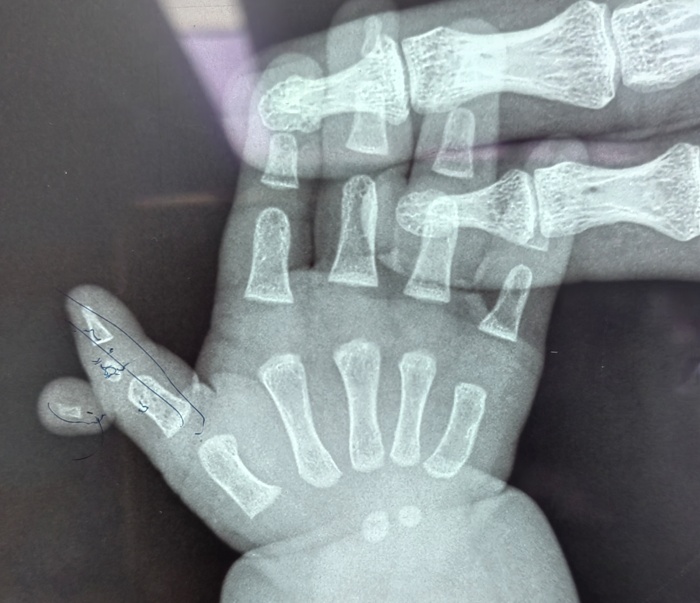

近日,在a片网站 的手术室内,一场特殊的手术正在进行。手术台上,一位仅六个月大的女婴安静地躺着,她的右拇指旁多出一个发育不全的指节,这个多余的手指像影子一样跟随着拇指移动,同时右拇指又长又歪,虽然不影响生命,但却严重影响了患儿手部功能的正常发育。

据孩子的妈妈介绍,孩子一出生,他们便发现了异常,孩子右手拇指较正常手指明显歪斜并且比左手的拇指要长,且在这根手指外侧,还多出来一截手指。多余的手指长在拇指指间关节处,虽然有指甲、有手指形态,但因为发育不全而缺乏自主活动能力。考虑到孩子年龄太小,家长一直未敢轻易做出治疗决定。

手术当天,骨科医护人员制定了周密的手术方案。在精准地切除了多余的手指后,切除了Delta骨块,修复韧带并予克氏针固定,对畸形的拇指进行了矫正。最终,患儿的右拇指恢复了正常形态。术后,患儿在医护人员的精心护理下逐渐康复,小手也变得更加灵活。医护人员高超的技术和优质服务,也赢得了家长由衷的感谢。

据骨科主任高凤奇介绍,三节拇指合并多指畸形并不常见,正常的多指多在一周岁以后手术治疗,多指的切除相对简单,但是三节拇的矫形较为复杂。合并Delta骨块的三节拇指合并多指一定要早期治疗,最早可以在六个月即可手术,越早做手术效果越好,a片网站 儿童骨科是长春市“十四五”医学重点专科,是吉林省内唯一一家专业的儿童骨科科室,历史悠久、综合实力雄厚。对于常见的儿童先天性肌性斜颈、多指、先天性髋关节脱位,以及复杂的四肢畸形、骨关节感染等有着丰富的治疗经验。